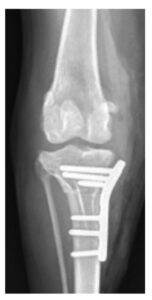

症例1. TPLOを実施した症例(7歳、ビーグル、9 kg)

| 治療前(側方像) | 治療後(側方像) | 治療前(前後像) | 治療後(前後像) |